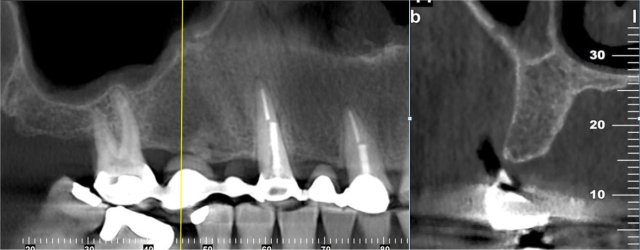

CBCT Implant Imaging

Show bone volume, nerve canal in the lower jaw, sinus floor on upper jaw. Other relevant anatomy can be identified to see if adequate bone is available for implant placement.